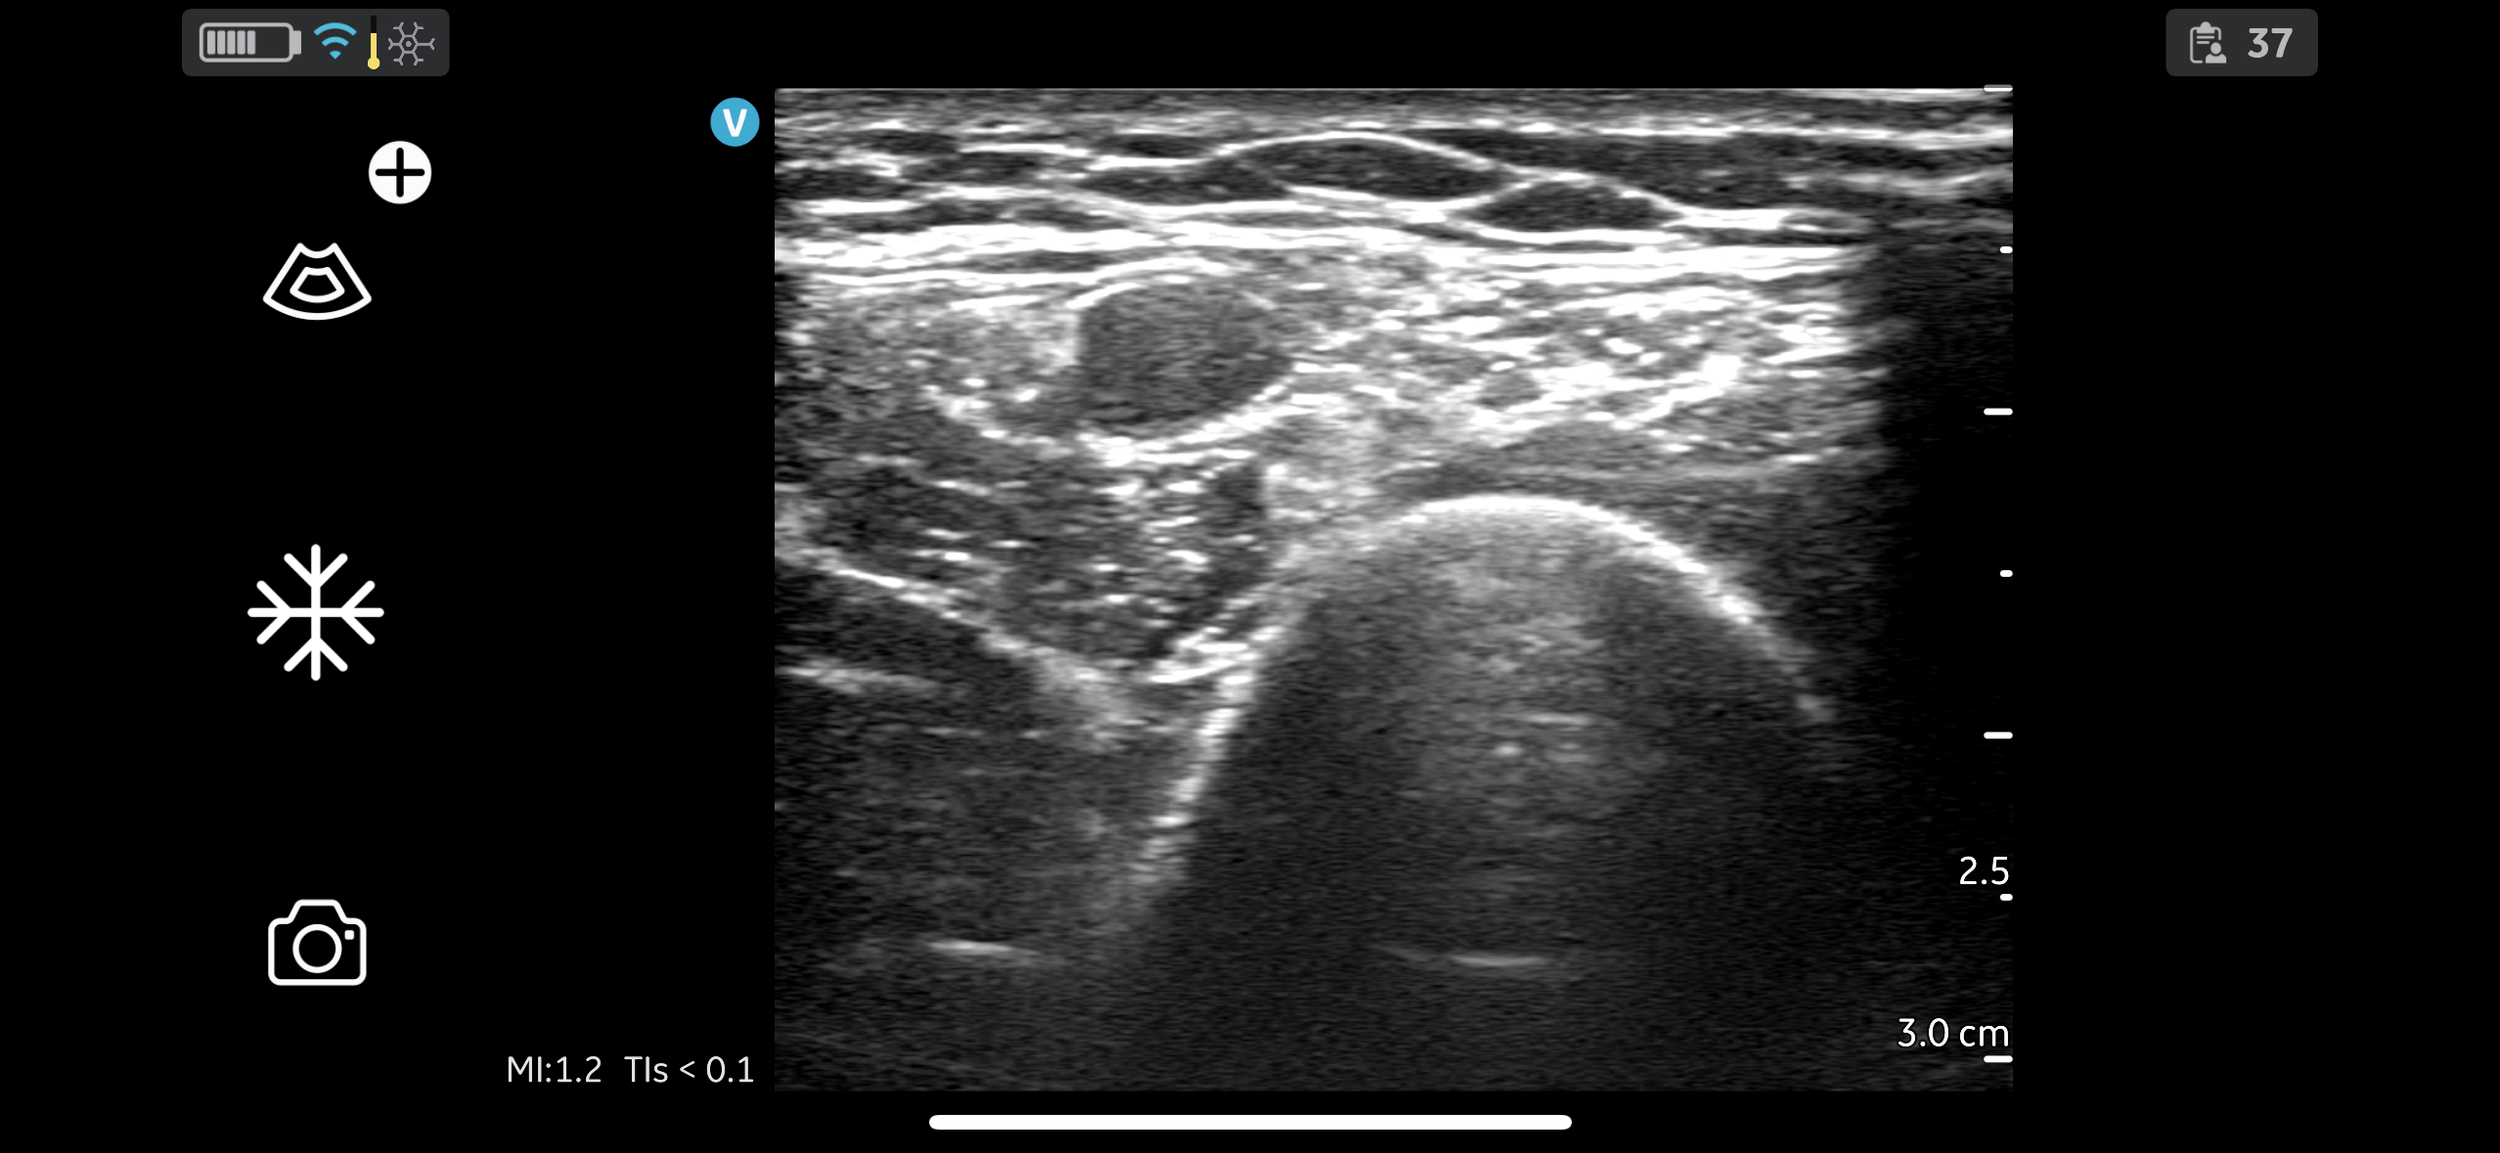

To make doctors, principally anaesthetists in the Thames Valley region, more enthusiastic about, and more confident and skilled in the provision of regional anaesthesia.